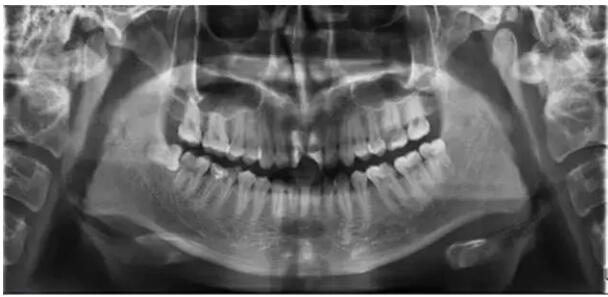

通过全面询问病史,临床检查和拍摄X光片,结合患者的主观症状、身心状态,拟定治疗方案,充分进行医患交流并详细记录。

四、确认根管工作长度

应用平行投照X线方法、根管长度测量仪确定根管长度 ,最好的办法是:技术+经验+根管长度测量仪+ X线 。